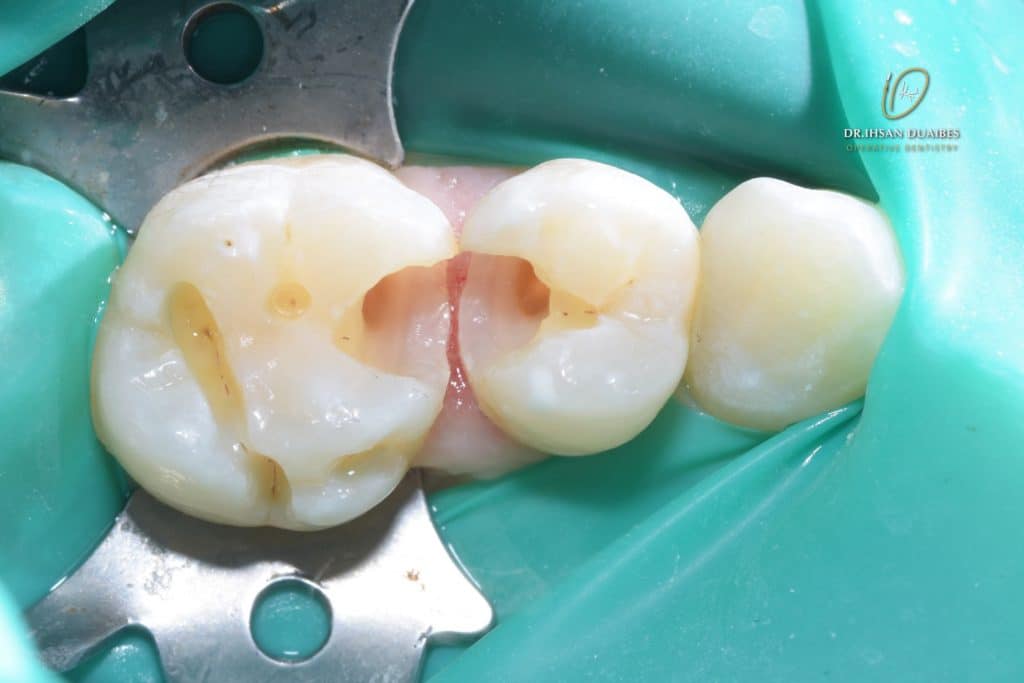

Now , put the gic and then finish the appointment, after the initial observation (to make sure that there are no symptoms) reduce the gic to make a permanent restoration using composite

After initial observation ( GIC reduction )

Choosing correct wedge and matrix stripes

Matrix